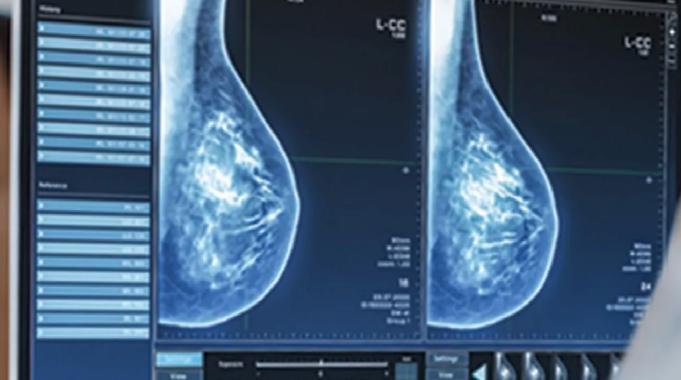

Meme kontrolünün nasıl olması gerektiğini anlatan Poçan, “Memedeki problemleri tespit etmek için yaş fark etmeksizin, kendi kontrollerimizi aksatmamalıyız. Kontrollerde bir problem tespit ettiğimizde ya da kırk yaş üstünde ise bir hekim tarafınca kontrol, meme ultrasonu, gereklilik halinde mamografi veya meme MRG ile tetkikleri gerekmektedir. Ülkemiz sağlık politikalarınca mamografi ön planda tutulsa da teknolojik gelişmelerin ultrason cihazlarında yapmış olduğu belirgin gelişim nedeniyle meme ultrasonu ile değerlendirme hem güvenilir hem de değerlidir” dedi.

Meme Ultrasonu, Mamografi ve Meme MR’ı hakkında da bilgiler veren Dr. Poçan,“Her üç yöntem de meme kanseri taramasında önemli rol oynar, ancak uygulama durumuna, hastanın özelliklerine ve risk faktörlerine göre tercih edilir” şeklinde açıklamalarda bulundu.